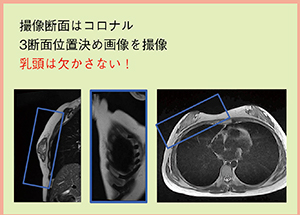

撮像は,3断面の位置決め画像を撮像後,コロナル断面で撮像を行っている。RVSフュージョンは乳頭で位置合わせを行うため,必ず乳頭を含め,腋窩リンパ節も観察できるように撮像断面を決定する(図3)。造影剤は2mL/sで注入し,患者には毎回同じ深さで呼吸停止するよう指示する。

図3 RVS用MRI撮像のポイント |

RVS用MRIの撮像のポイントとして,(1) 使用シーケンスは脂肪抑制併用3D-GRE,(2) 自動注入器を用いたダイナミック撮像,(3) 体幹部コイルを用い,コイルは患者に触れないよう配置,(4) 腋窩リンパ節を意識し,乳頭を欠かさず撮像の4点が挙げられる。MRI装置の進歩は著しいものがあり,各メーカーさまざまなシーケンスが存在する。MRI装置の特色を生かし,今後もRVSに有用な画像提供に努力していきたい。